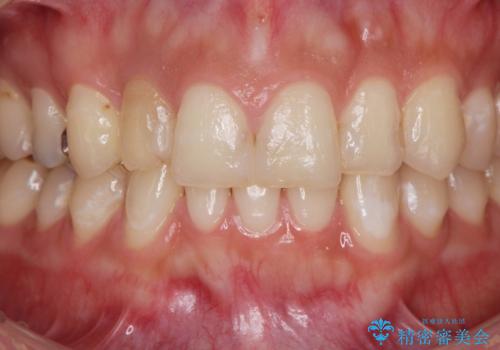

充填物の変色を繰り返す前歯のセラミック治療

- 神経をとった前歯の変色や、前歯の充填物の変色が大きくなってきたので審美性の改善を求めて来院されました。

充填物や充填物下に再発した虫歯を丁寧に除去し、セラミッククラウンによる審美性の改善、虫歯治療を計画します。

レジン修復による充填は、劣化し、色調の変化による審美障害が生じることが多々あります。

ある程度の大きさになった充填物は、劣化の少ないセラミッククラウンにすることで色調の劣化を抑え、審美性を保つことができます。